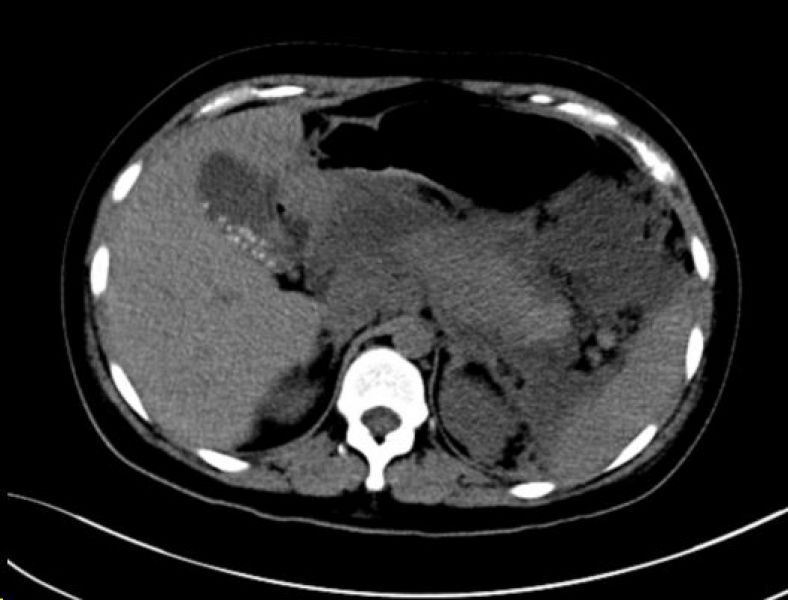

出院时CT影像

返回肝胆二病区后,患者继续抗胰腺炎治疗,经过精心的专科治疗,腹痛症状逐渐缓解,复查淀粉酶等逐渐恢复正常,复查腹部CT胰腺周围渗出较前吸收,胰腺有假性囊肿形成可能,患者目前未出现发热腹痛等症状,胃肠道功能已恢复,病情稳定出院,只待胰腺炎恢复后,再返院处理胆囊结石及胰腺假性囊肿,于是出现了病房内和谐欢乐的一幕。